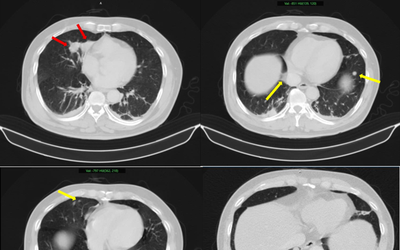

Người đàn ông 70 tuổi, tưởng cảm cúm hóa ra phổi “trắng xóa”: Biết "thủ phạm" nhiều người hoang mang

Sức khỏe Thứ 3, 26/05/2026 | 04:00

Tưởng chỉ là một đợt cảm cúm thông thường, người đàn ông 70 tuổi không ngờ chỉ vài ngày sau đã rơi vào suy đa tạng với hai lá phổi “trắng xóa”, và nguyên nhân lại ẩn ngay trong thói quen sinh hoạt quen thuộc của rất nhiều gia đình.